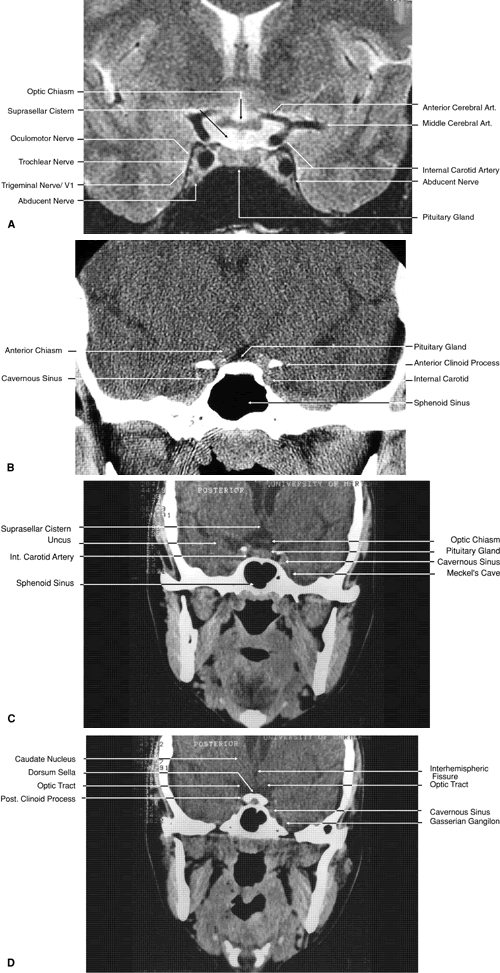

Fig. 27. Coronal images through cavernous sinus and optic chiasm. A. T1-weighted magnetic resonance imaging through anterior chiasm. B. Computed tomography image through anterior chiasm. C. Computed tomography image through posterior chiasm. D. Computed tomography image through optic tract.

Fig. 28. Axial computed tomography image with contrast medium through cavernous sinus and pituitary gland.

The globe is shown in Figure 12. The orbit and periorbital structures are shown in Figures 13 through 16, and the optic canal is shown in Figures 17 through 26. The cavernous sinus and optic chiasm are shown in Figures 27 and 28, and the posterior visual pathway and cranial nerves are shown in Figures 29 through 33.